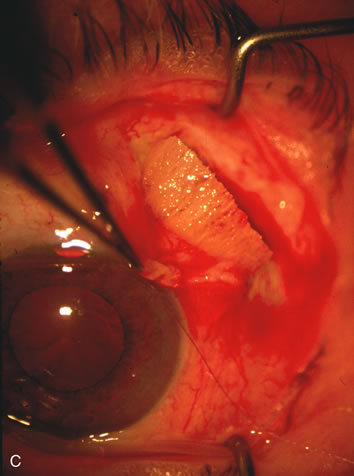

Fig. 3. Partial bleb failure following clear corneal phacoemulsification with foldable IOL. A. Preoperative bleb appearance prior to temporal lens extraction. Preoperative IOP was 12 mm Hg on no antiglaucoma medications. Time from 5-FU trabeculectomy surgery to lens extraction was one year. B. Bleb appearance 2 months after clear corneal cataract surgery with topical anesthesia. Following lens extraction, increased vascularity was noted along with decreased size of the filtering bleb. IOP increased to 20 mm Hg as early as 2 weeks after surgery, necessitating topical antiglaucoma therapy. C. High magnification view of bleb before lens extraction demonstrates diffuse pale bleb. D. High magnification view of bleb 2 months after surgery. There are vessels surrounding the nasal side of the bleb and the overall bleb size is smaller.

Fig. 1. The anatomic advantage of small incision cataract surgery for the glaucoma patient. A. Long-term bleb function with a large cataract incision is difficult to achieve with either ECCE-trabeculectomy or trabeculectomy followed later by ECCE. This bleb failed to form sufficiently when combined with large incision ECCE. The inflammation, bleeding, and long-term wound healing with stimulation of fibroblasts associated with this technique are more likely to cause bleb failure. In addition, the increased iris manipulation necessary to deliver the nucleus and subsequent iris repair adds to the long-term breakdown of the blood aqueous barrier. B and C. Two-site phacotrabeculectomy has the advantage of small incision cataract surgery combined with separate site trabeculectomy. The incision size is one third the size of the standard ECCE. The inflammation is less severe, and cataract wound healing is confined to the temporal area. Visual rehabilitation with phacoemulsification and foldable IOL is much faster. Phacoemulsification allows successful lens extraction even in the unfriendly environment of a smaller pupil compared with ECCE. The trabeculectomy is performed in an entirely different site, well away from the wound healing associated with temporal phacoemulsification. The likelihood of this filter functioning long-term is greater than with ECCE-trabeculectomy. D. The surgeon also has the option of single-site phacotrabeculectomy with foldable IOL. Both the lens extraction and trabeculectomy are performed through one small 3.5-mm limbal incision.